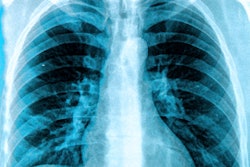

While you're in the community, check out this article on an AI project conducted by Google engineers, who developed an algorithm for interpreting x-rays. And learn about a new partnership between two influential radiology organizations to foster the development of more useful AI algorithms.